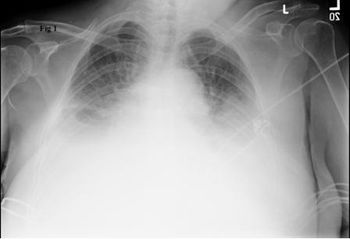

Recovery from a hemopneumothorax had progressed well for this 29-year-old man until today when he presents to the ED with dyspnea and pleuritic chest pain. What do you see on the chest x-ray?

Persistent symptoms of hemothorax or pneumothorax, in the absence of new x-ray findings require further inquiry, including chest CT, to rule out PE.